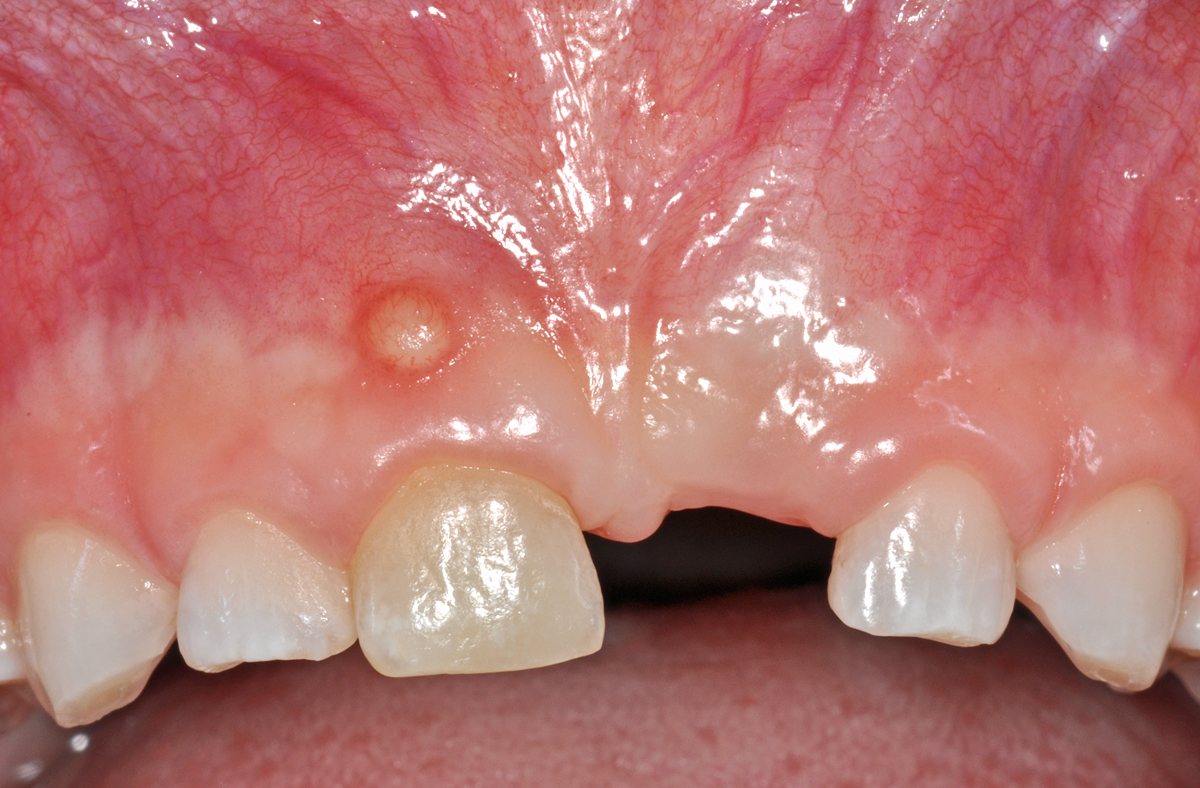

Dieser Fall zeigt einen knapp 7 Jahre alten Patienten, der sich schon vor einiger Zeit bei einem Sturz mit dem Fahrrad den mittleren Milch-Schneidezahn oben links (61) herausgeschlagen hat.

Offensichtlich ist dabei auch der rechte obere mittlere Milch-Schneidezahn (51) in Mitleidenschaft gezogen worden, denn er wurde anlässlich einer Kontrolle ein Jahr zuvor schon als verfärbt notiert (das ist auch auf den Bildern zu erkennen). Bei der neuerlichen Kontrolle zeigte sich an der Mundschleimhaut oberhalb des Zahnes 51 eine kleine, rundliche Erhebung (Pfeil).

Dabei handelt es sich nach klinischer Beurteilung um einen kleinen Abszess (eine eitrige Entzündung), ausgehend vom Zahn 51. In vielen Fällen ist eine solche Entzündung bei Kindern chronisch und verläuft ohne oder mit nur sanftem Schmerz. Oft entleert sich der Eiter dieser Entzündung spontan; man spricht dann von einer Fistel.